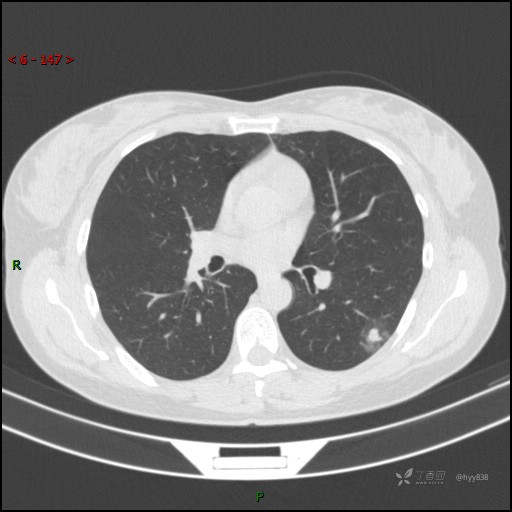

胸膜下“煎鸡蛋征”,感染 VS 炎症 VS 肿瘤,挑战有你---结果公布~

简要病史:干咳半月伴左胸部不适

辅助检查:CT

临床诊断:结节

讨论:病变性质?